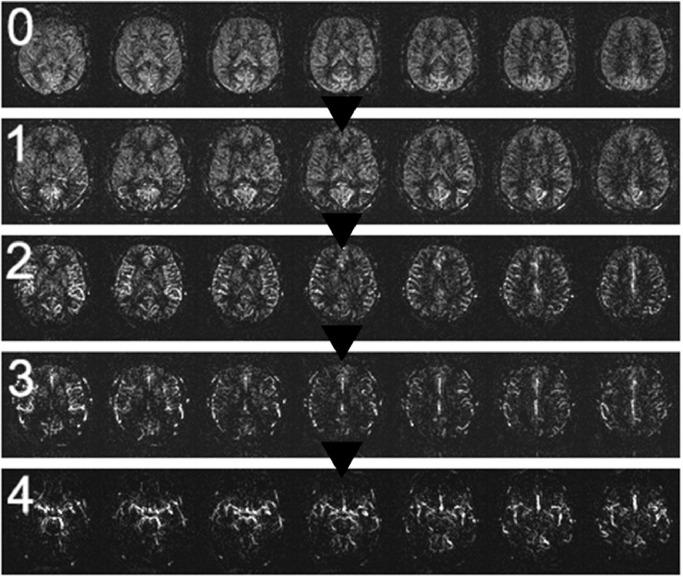

We employed a five-stage scale (0 being normal and 4 indicating the most severe perfusion decline) to assess 156 patients using a 3D pulsed ASL technique. Three radiologists independently reviewed the images, and inter-rater reliability of the visual rating scale was evaluated.

The ASL stages showed a consistent distribution among the patients. The inter-rater reliability among the three radiologists, as measured by the Intraclass Correlation Coefficient (ICC), was 0.982.

Our findings suggest that this visual rating scale can be effectively implemented in everyday practice to evaluate global perfusion changes in the context of cardiovascular diseases, cerebrovascular diseases, cerebral small vessel disease, and other conditions that alter brain vascularization and perfusion. Further research is needed to explore the full range of clinical applications and to refine the scale for optimal utility.